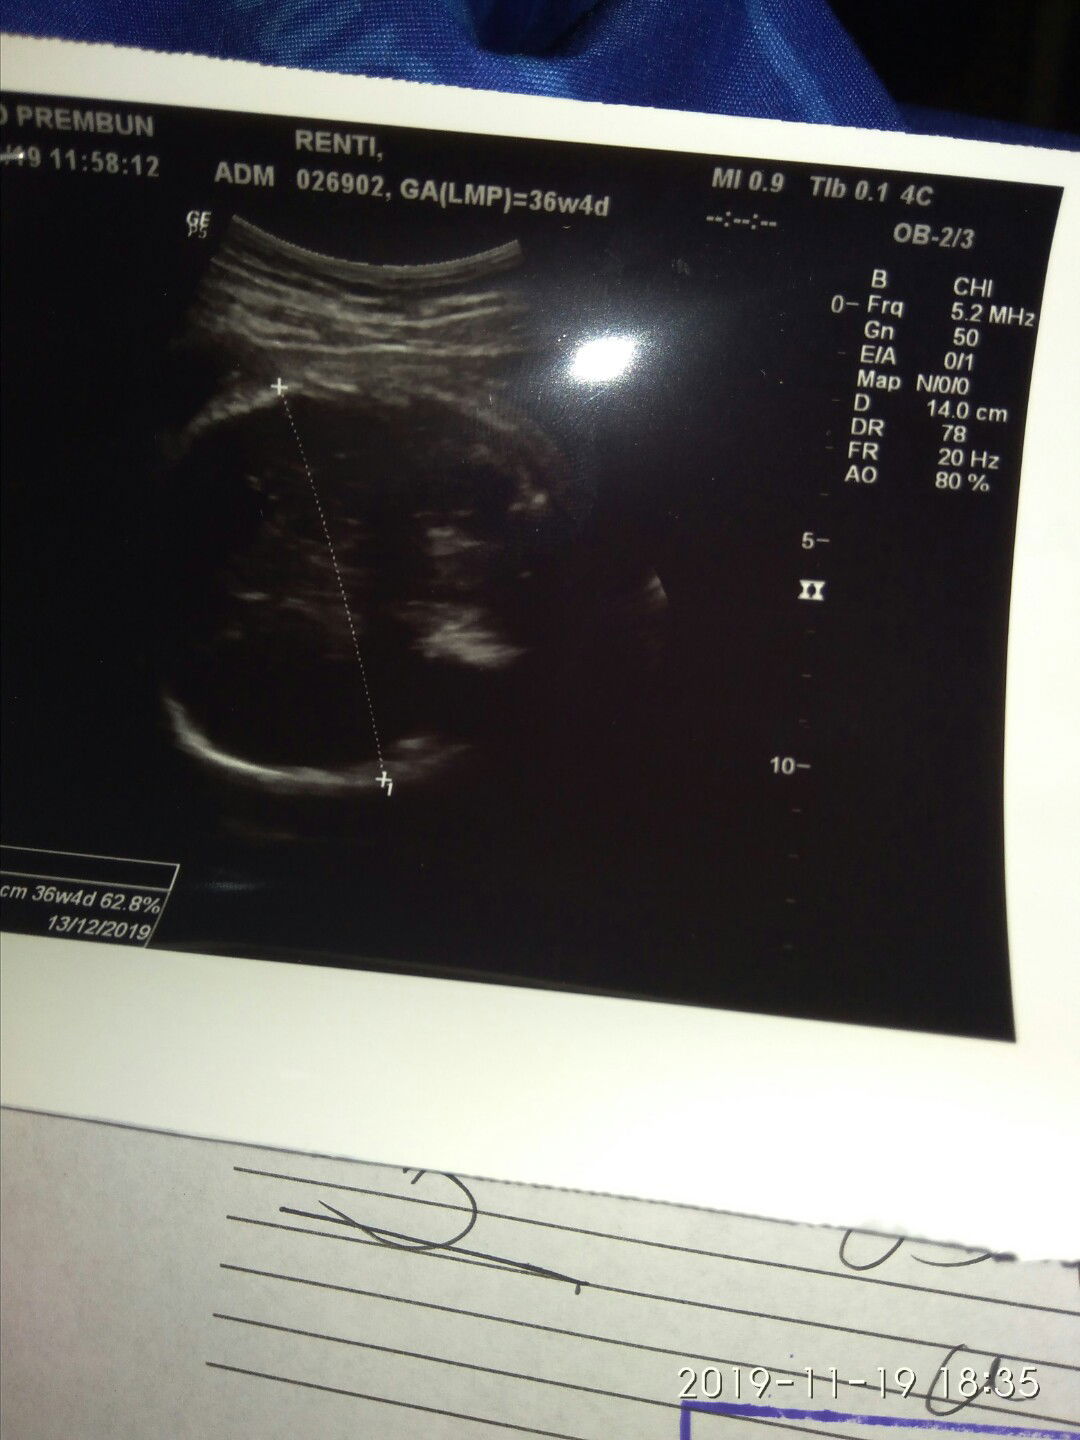

Allhamdulilah q sebelum melahirkan diberi semangat sama mamak+bapak ,suruh jangan teriak2 dan tetap tenang dan istifar yang ihklas dan serahkan semua pada Alloh SWT ,,,semoga dilancarkan persalinannya,.dan udah mulai pembukaan 5 #Semangat yang hplnya Desember semoga kalian bisa nikmati rasa sakit setiap prosesnya??